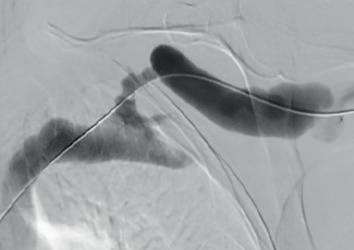

Example procedural outcome: treatment of Bond’s patient with a left brachiocephalic AVF that presented with a stenosis at the cephalic arch with aneurysmal segment.

(A) Fistulogram taken preintervention and (B) after deployment of WRAPSODY to treat. (C) Fluoroscopy of treated segment at 18 months (D) and patient’s arm at time of presentation

When asked why he chose Wrapsody CIE, he notes that, due to the anatomical anomaly present in this patient, no other endoprosthesis would have yielded a positive outcome. In addition, he indicates that the device’s design, specifically its tactile feel, made it a good treatment option. For Bond, the whole process was “very, very intuitive” and use of the device was “very straightforward”. As for the patient, he notes that she tolerated the procedure quite well: “The next day, the patient was achieving all of her dialysis

goals, and her pain was resolved overnight. She is due for her three-year angiogram this month— she has not had any issues with dialysis.”